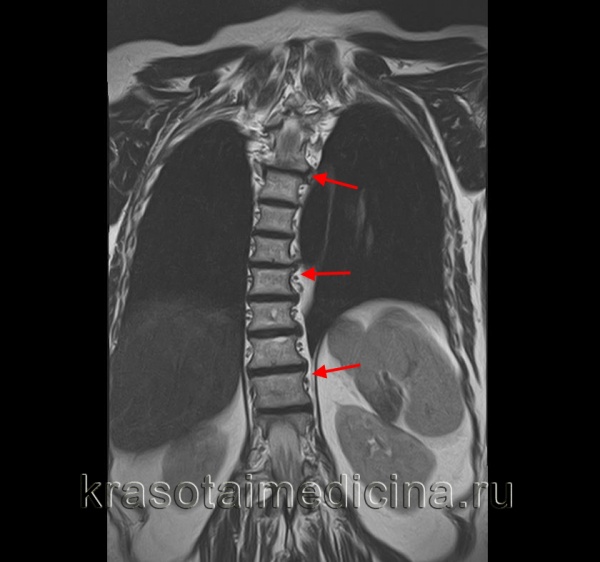

4. МРТ:

• Позволяет выявить аномалии позвоночника и спинного мозга, кистозные изменения, опухолевое и инфекционное поражение

МРТ грудного отдела позвоночника. Выраженная дугообразная сколиотическая деформация грудного отдела позвоночника вправо.